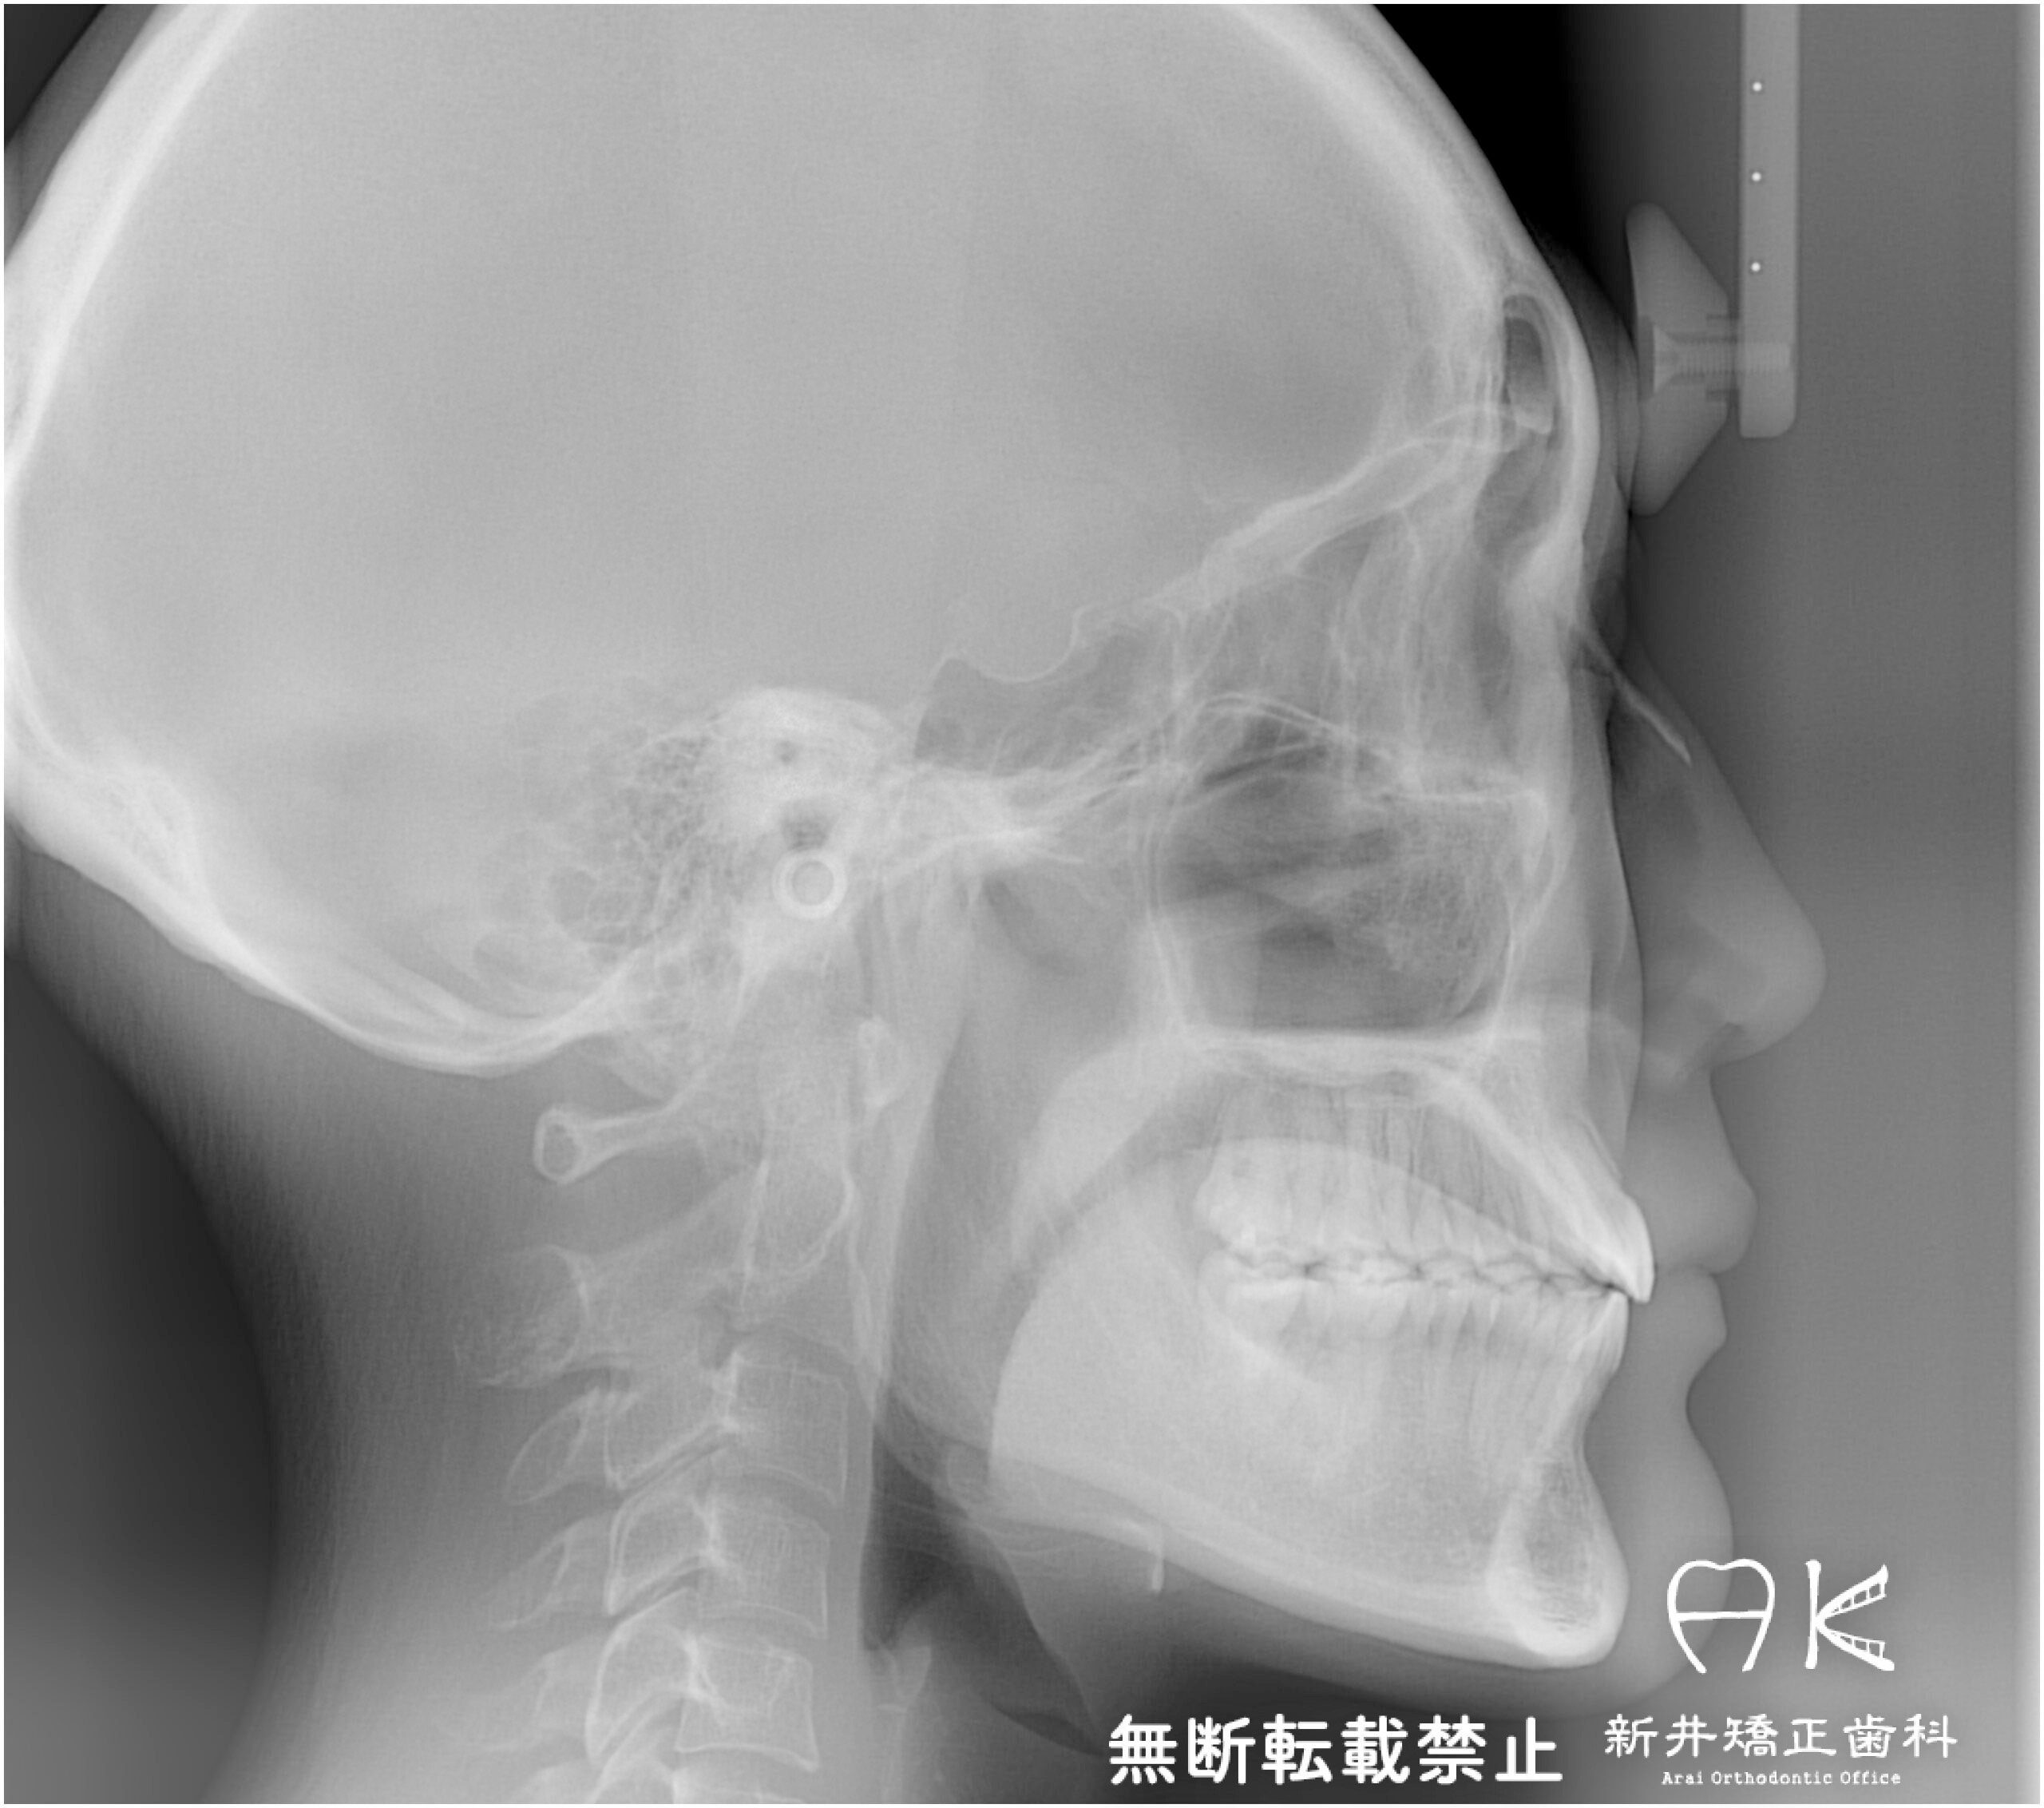

セファログラムのトレースの重ね合わせ(緑:治療前、赤:治療終了時)

治療前後の解説

| 治療前 | でこぼこしている歯による歯磨きのやりにくさや、奥歯がしっかり咬んでいない鋏状咬合(すれ違い咬合)。 出っ歯による口の閉じにくさ(口唇閉鎖不全)と、正面から見た時のオトガイ部にできる梅干し様のシワやイーラインから飛び出た口元(口ゴボ)。 機能面も審美面も気にしていた患者さんです。 治療中もなるべく装置を目立たせたくないため、ハーフリンガルでの治療となりました。 |

| 治療後 | 上下の歯がお互いにはまり込み、全体的に緊密な咬み合わせになっています。 出っ歯が治り、口元の突出感が改善されて綺麗なEラインを獲得しました。 すれ違い咬合や叢生(歯のでこぼこ)も治って歯磨きがしやすく、嚙みやすい状態になっています。 |